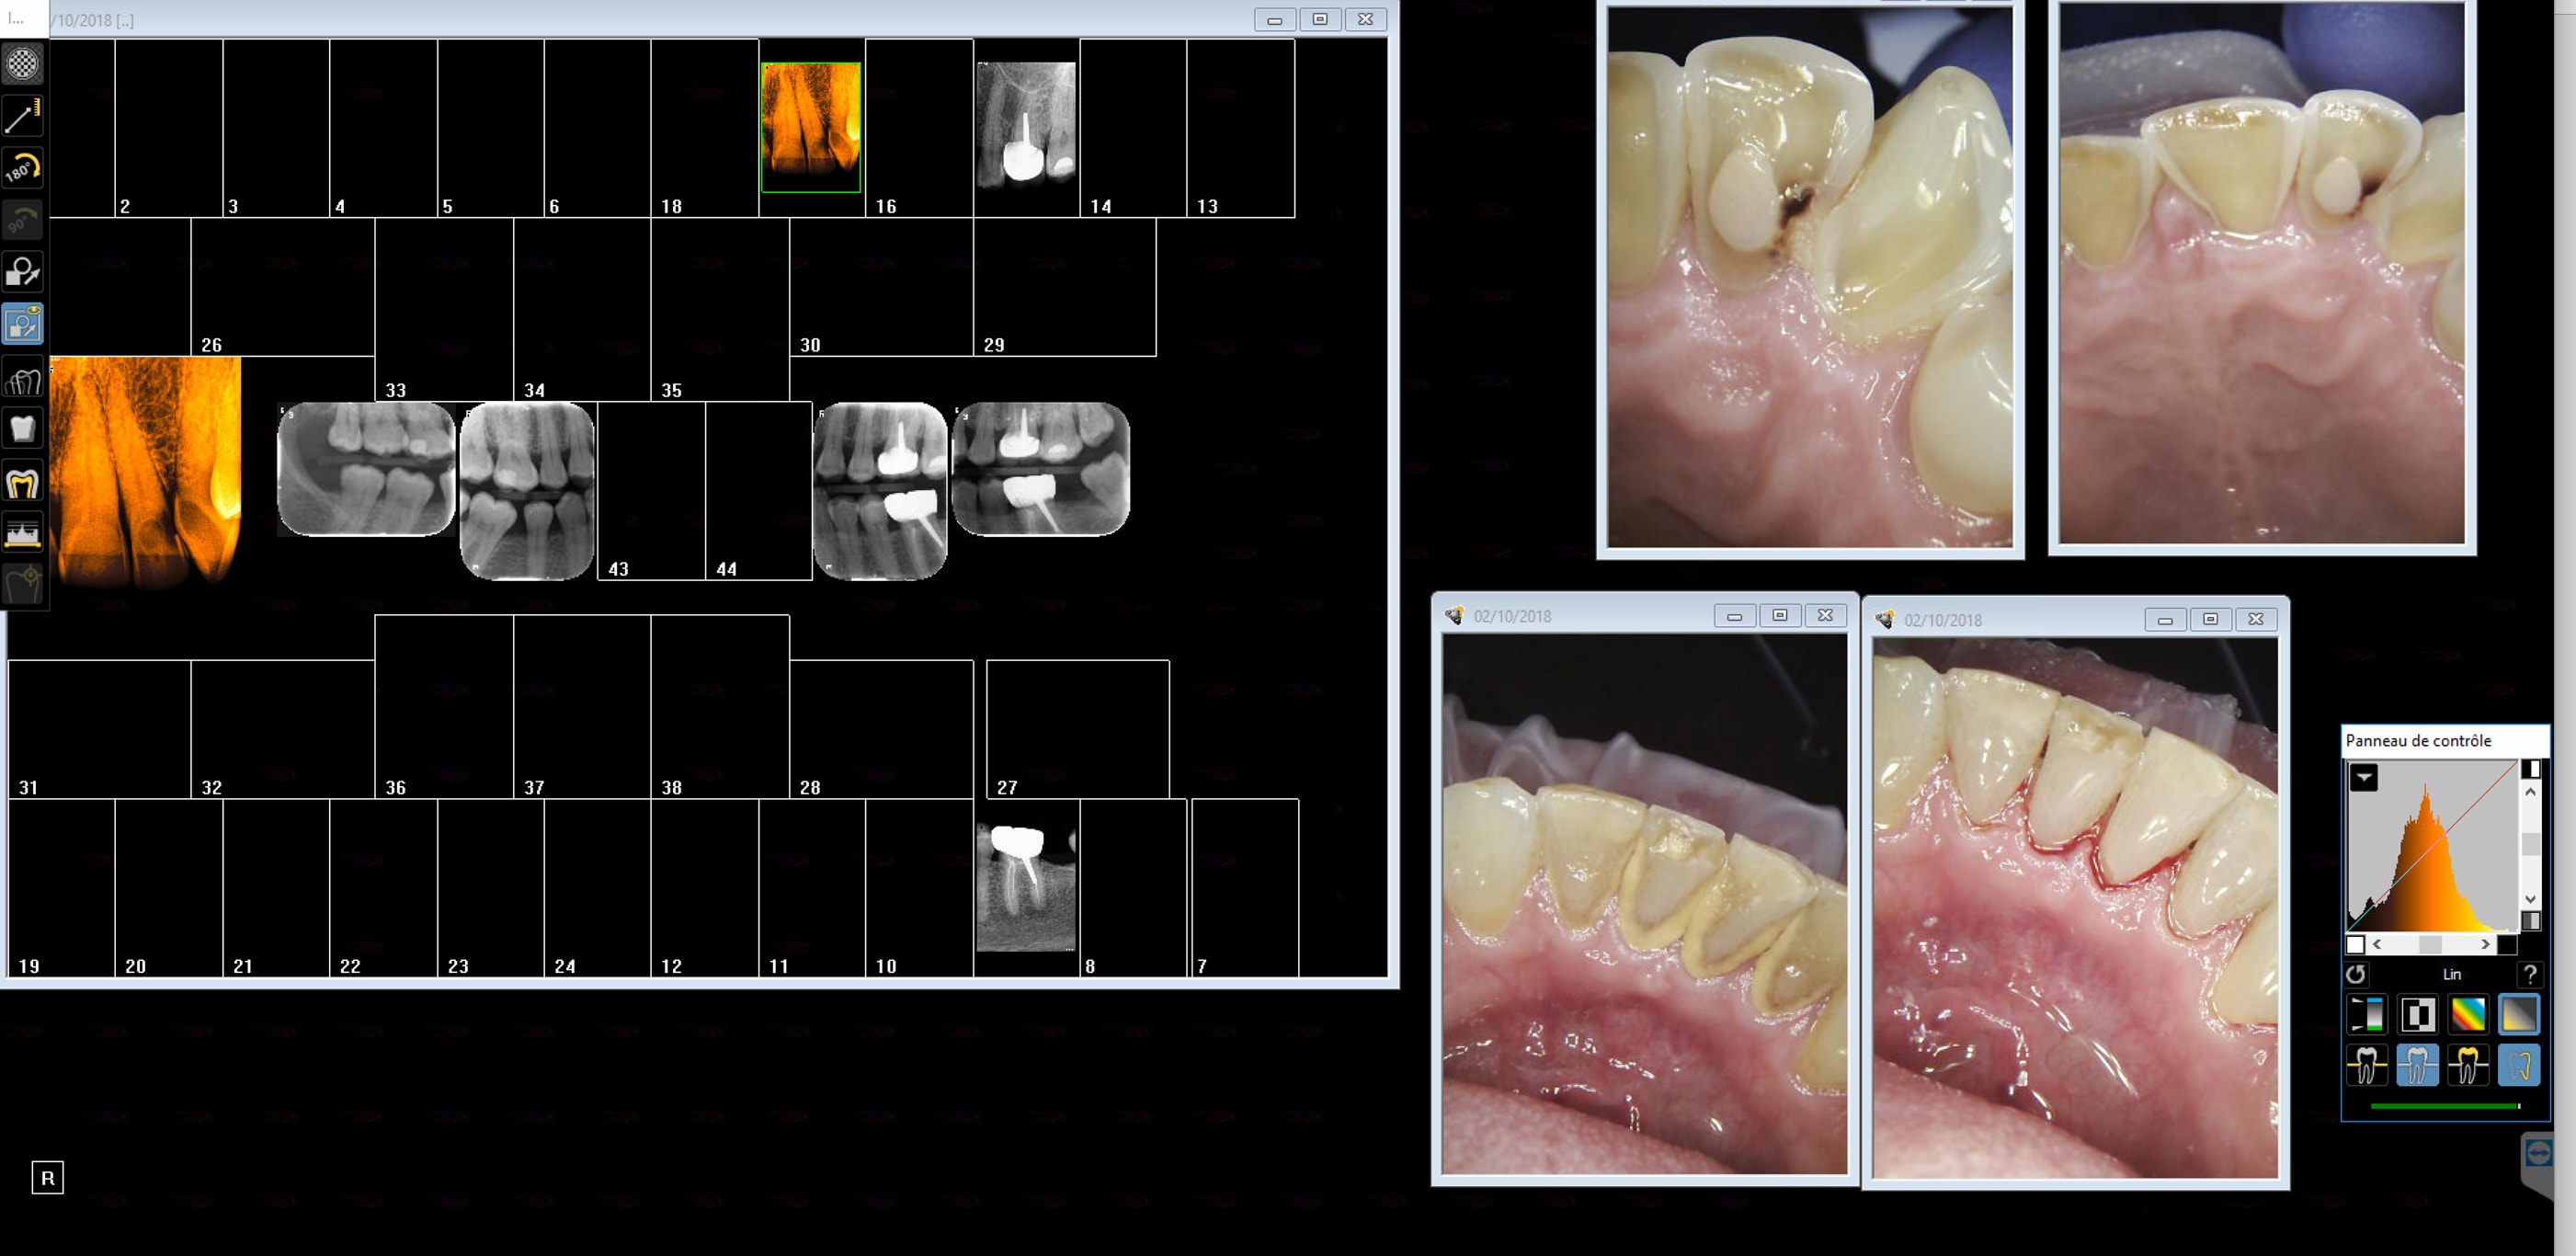

T'inquiètes celle ci a très bien compris pourquoi sa 22 la fait souffrir. Rétro coronaires + rétro alvéolaires si justifiées. Point.

Capture d écran 2018 10 03 00.05 - Eugenol